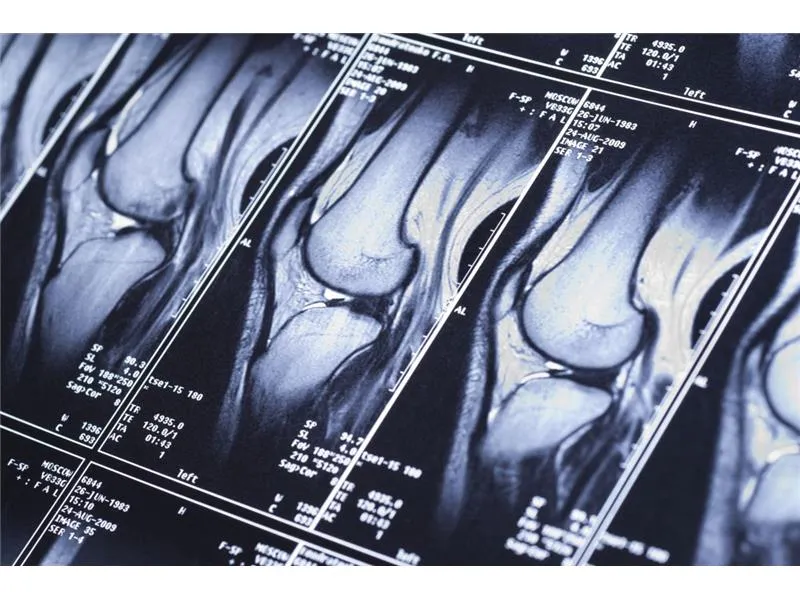

Lekarz rehabilitacji może wystawić skierowanie na rezonans magnetyczny w różnych sytuacjach medycznych, które wymagają dokładniejszej diagnostyki. Skierowanie na MRI jest szczególnie uzasadnione, gdy inne metody diagnostyczne, takie jak zdjęcia rentgenowskie czy ultrasonografia, nie dostarczają wystarczających informacji. Przykłady takich sytuacji obejmują przypadki, gdy pacjent cierpi na chroniczne bóle stawów, urazy sportowe czy podejrzenia uszkodzeń tkanek miękkich.Warto zaznaczyć, że lekarz rehabilitacji może również kierować na MRI w przypadku podejrzenia schorzeń neurologicznych, takich jak stwardnienie rozsiane czy uszkodzenia rdzenia kręgowego. W takich przypadkach rezonans magnetyczny dostarcza cennych informacji, które mogą pomóc w dalszym planowaniu terapii. Ostateczna decyzja o skierowaniu na badanie powinna być oparta na dokładnej ocenie stanu zdrowia pacjenta oraz jego objawów.

- Urazy sportowe, takie jak skręcenia czy naciągnięcia, które wymagają dokładnej oceny tkanek miękkich.